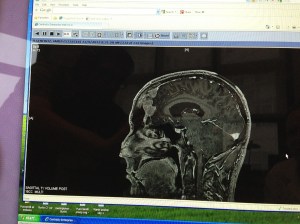

By this time tomorrow the parasaggital meningioma resting behind my skull will have been removed. I am scheduled for operation tomorrow at noon, and I am working right now to make sure that I am properly prepared mentally, physically, spiritually, and otherwise.

I’ve been asking myself how best to prepare for something like this, and I’ve been eager to start sharing thoughts here. With no clear idea where to start, I turned to these images. I have so much to say about these images and this topic, but for the moment I want to let the visuals speak for themselves.